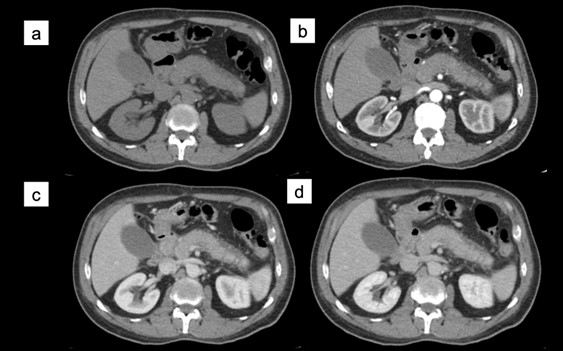

La duplicación esofágica es una de las anomalías benignas del desarrollo embrionario del intestino anterior. Su causa es idiopática, se estableció una teoría relacionada con la anomalía de la vacuolización esofágica (…).